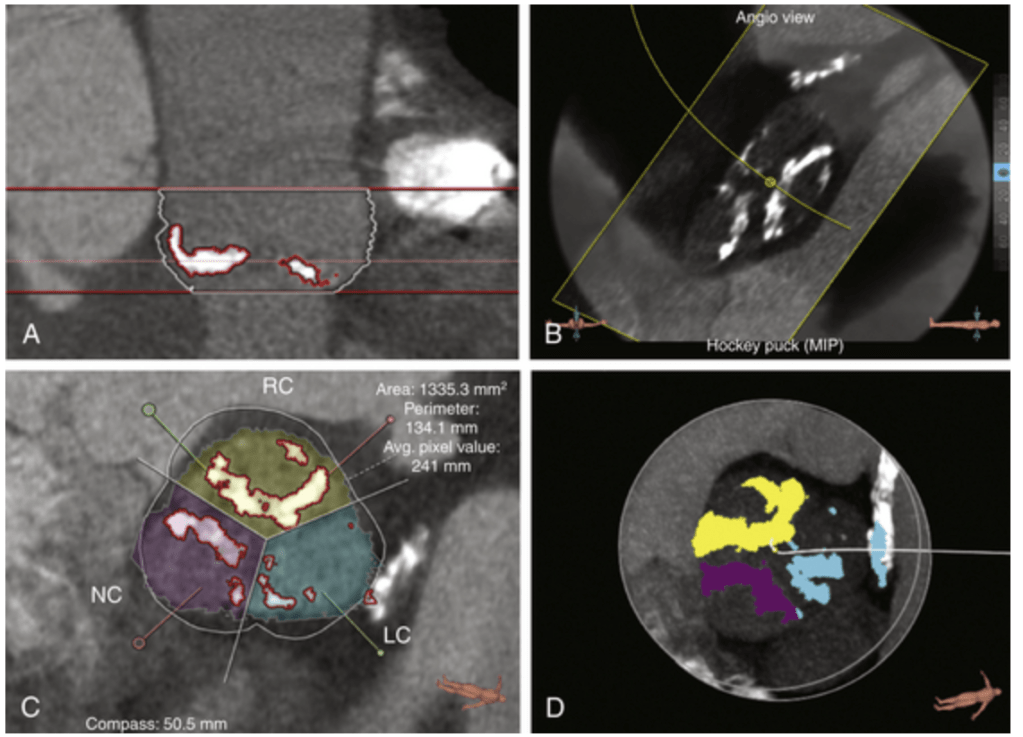

Image courtesy : Thoracic Key  Assessment of aortic valve calcification.The stretch view shows dense calcification of the right coronary cusp, noncoronary cusp, and left coronary cusp. The stretch view (A), angiographic overlay (B), cross-sectional view (C), and “hockey puck” view (D) allow quantification of the calcium in the aortic valve.